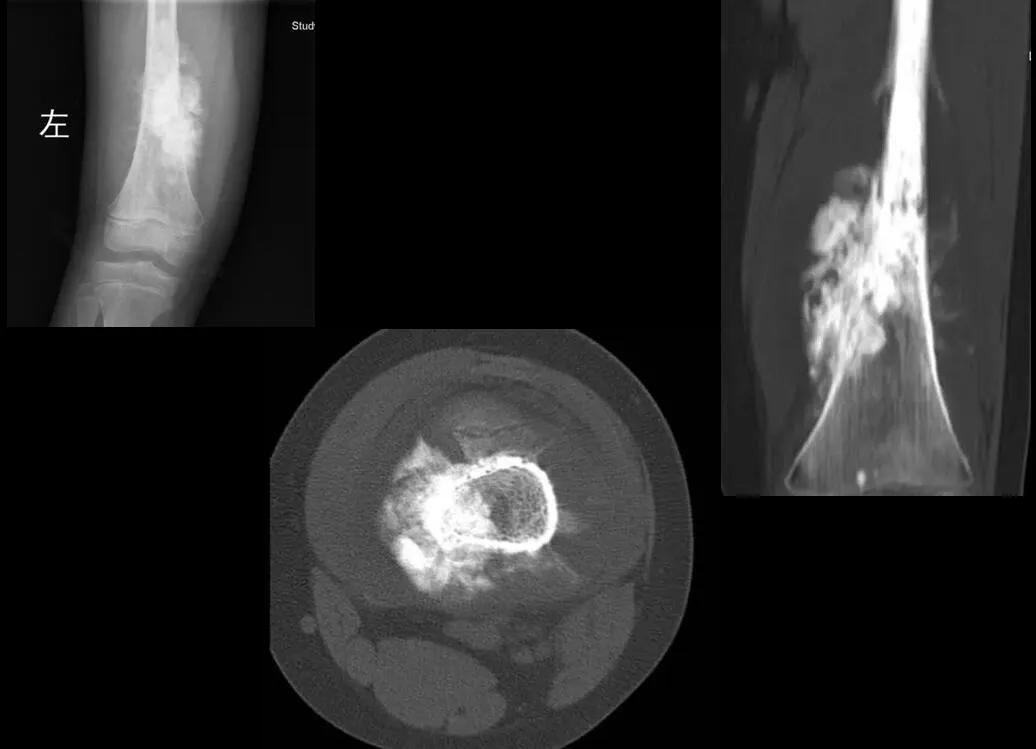

骨肉瘤可发生于任何骨。国内统计资料显示最常发生于股骨(47%),其次为胫骨(26.3%),其余依次为肱骨(7.1%)、颌骨(5.1%)腓骨(3.8%)及骨盆(2.7%)。肿瘤好发于长骨干骺端,尤其是股骨远端和胫骨近端最多见。X线平片检查,骨肉瘤有以下基本表现:骨质破坏:多始于干骺端中央或边缘部分,骨松质呈小斑片状骨破坏,皮质边缘可见小而密集的虫蚀样破坏区,在皮质内表现为哈弗斯管扩张而呈筛孔状破坏;以后骨破坏区融合扩大形成大片的骨缺损。肿瘤骨:骨破坏区和软组织肿块内的肿瘤骨是骨肉瘤本质的表现,也是影像诊断的重要依据。骨膜反应和Codman三角:骨肉瘤可引起各种形态的骨膜反应和Codman三角,两者虽是骨肉瘤常见而重要的征象,但并非特异,也可见于其他骨肿瘤和非肿瘤性病变。

典型骨肉瘤X线表现为长骨干骺端髓腔内边界不清的骨质破坏区,穿破骨皮质生长并软组织肿块形成,内见瘤骨、Codman三角(或)日光照射样骨膜反应,有时可发生病理性骨折。

应当强调的是,对于大多数骨肉瘤的患者,凭X线平片基本上可作出诊断,但CT或MRI是必不可少的补充。

CT除了与MRI一样有利于发现平片上不易显示部位的病变外,由于其对细小的骨化和钙化敏感,当平片上不能确定有无瘤骨或瘤软骨钙化时,CT对确定骨肉瘤的诊断有重要意义。